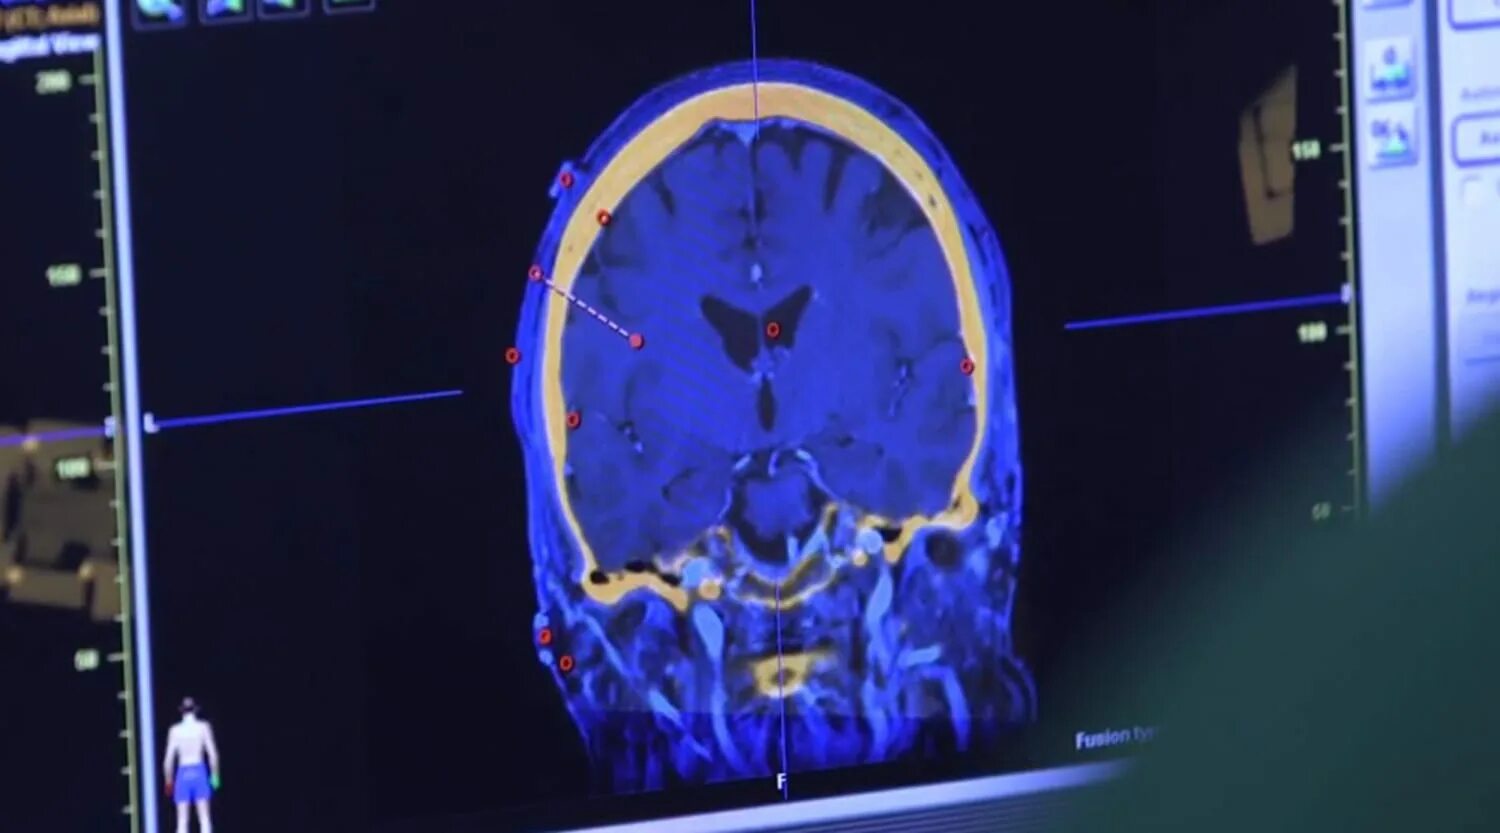

Как умирают от рака головного мозга